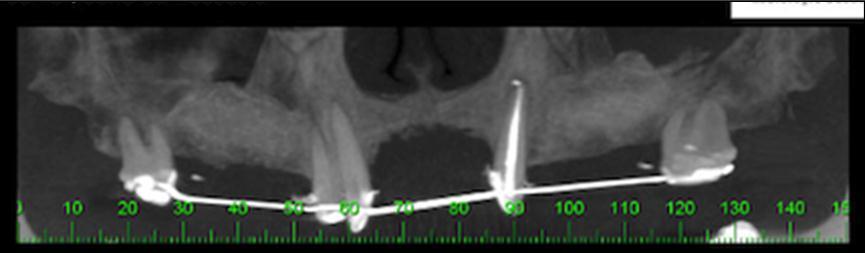

A 49-year-old female presenting a severely resorbed pre-maxillary as a result of previous autogenous bone graft presented to the clinic. Treatment plan was conducted by means of the fabrication of a prototype anatomic model by means of a CBCT scan (Figure 1). A titanium mesh was fabricated on this model to shape an ideal ridge, with normal height and width. Four dental implants were planned to substitute teeth number 7, 8, 9 & 10 for single unit crowns.

Figure 1.CBCT showing presence a significant bone defect of the pre-maxilla.